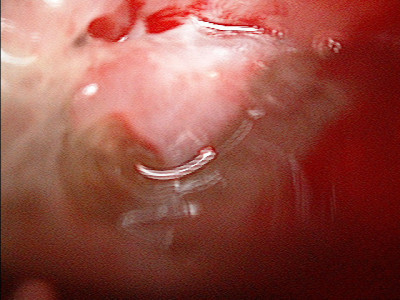

Absceso pleural apical posterior